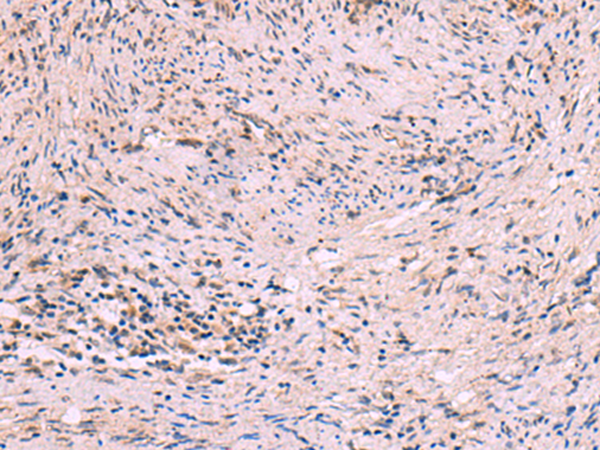

IHC positive control: |

Human cervical cancer |

IHC Recommend dilution: |

10-50 |